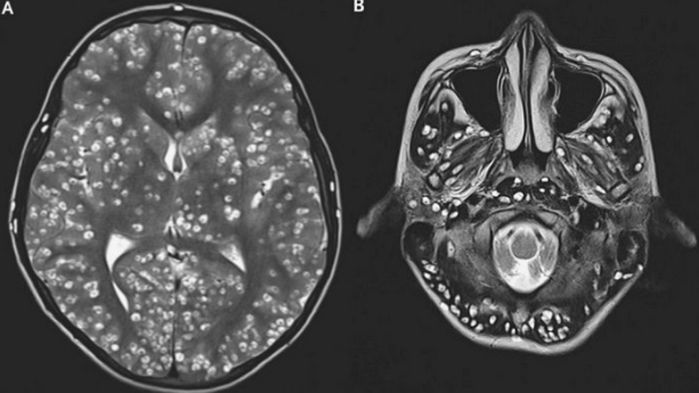

MRI 촬영 결과 낭종 병변으로 뒤덮인 소년의 뇌 / Dailymail

의료진이 실시한 MRI 촬영 결과는 가히 충격적이었습니다. 소년의 뇌 전체에 수백 개의 미세한 구멍이 뚫려 있는 듯한 모습이 포착된 것입니다. 이 구멍들의 정체는 다름 아닌 '낭종 병변'이었으며, 의료진은 이를 기생충 감염에 의한 '신경낭미충증'으로 진단했습니다.